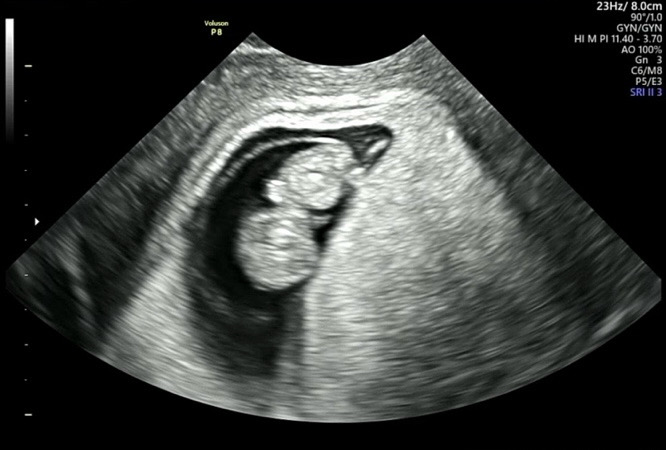

저번에 심장소리 처음 듣고 두 번째 초음파 찍고 왔어요! 잘 있나 걱정됐는데 2등신(?)의 젤리곰이 절 맞아주네여~팔도 생겨서 팔딱팔딱🥹 담당쌤은 눈사람 같다며ㅎㅎㅎ 그런데 머리가 좀 큰 것 같기도 한..요새 초코만 먹어서 그런가ㅠ별게 다 걱정인 초보맘입니당..담에도 건강하게 보쟈~👶💕